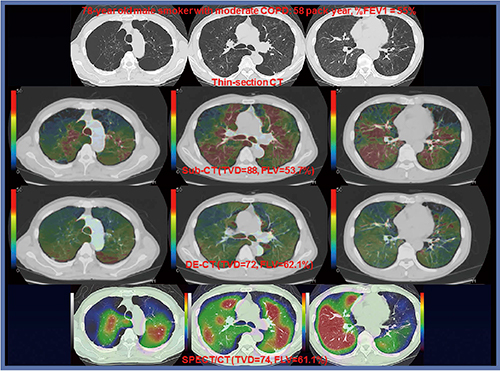

本手法は,Dual Energy CTやVentilation SPECT/CTと同様にXenon の造影効果によって肺内換気を画像化することが可能であり(図3)10),喫煙などに伴う肺機能障害や慢性閉塞性肺疾患(COPD)の重症度評価が可能であることが知られている。したがって,今後,本手法を形態診断と併せて行うことにより,現在まで明らかにされていないさまざまな換気障害を画像化することが可能であり,気道疾患やさまざまな呼吸疾患の病態生理を解明することも可能になり,新たな画像診断学を確立することも可能であろうと期待できる。

図3 喫煙に伴うCOPD患者におけるSubtraction ADCT(Sub-CT)およびDual Energy

ADCT(DE-CT)によるXenon-Enhanced ADCTとKrypton SPECT/CT DE-CTと同様にSub-CTにて肺内換気を画像化することが可能であり,Xenonによる造影効果はSub-CTの方がDE-CTよりも高いため,局所換気の差を明瞭に描出でき,Krypton SPECT/CTとの換気不均等の一致率も高い。